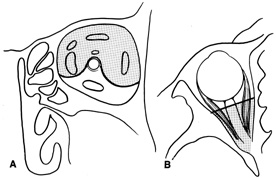

The other important consideration in planning orbitotomy is the position of the tumor within the orbit. Lesions generally may be categorized as either anterior (superficial) or posterior (deep). They can be further categorized by their relationship to the optic nerve (medial, lateral, superior, or inferior to the optic nerve). It may be helpful to further classify the location of lesions relative to adjacent anatomic structures in the orbit. Many surgeons prefer to conceptualize orbital pathologic processes as being located within one or more of seven “surgical spaces” within or around the orbit (Fig. 5). These spaces include:

Fig. 5. Axial drawing of anatomic spaces of the orbit. (1, intraconal space; 2, extraocular muscles; 3, peripheral surgical space; 4, subperiosteal space; 5, preaponeurotic space; 6, Tenon's space; 7, periorbital tissues.)

1. Central surgical space (intraconal space)

2. Extraocular muscles

3. Peripheral surgical space (extraconal space)

4. Subperiosteal space

5. Preaponeurotic space

6. Tenon's space

7. Periorbital tissues

The central surgical space is bounded by the intermuscular septum, which connects the four rectus muscles in the coronal plane. This space also is described as the retrobulbar or intraconal space, and it contains the optic nerve, intraconal fat, and various vascular and neural structures. Primary orbital tumors such as cavernous hemangiomas or optic nerve meningiomas originate in the central surgical space.

Many orbital processes involve the extraocular muscles, primarily or secondarily, making it useful to classify the extraocular muscles as residing in their own separate surgical “space.” Conditions affecting the extraocular muscles include thyroid orbitopathy, myositis, and a variety of neoplastic conditions.

The peripheral surgical space, also known as the extraconal space, lies outside the intermuscular septum but within the periorbita. This space contains a scant amount of orbital fat, the superior oblique muscle and trochlea, inferior oblique muscle, and lacrimal gland. Other important nerves and vessels extend into the space, such as the superior ophthalmic vein. A variety of pathologic processes may encroach on the peripheral surgical space.

The subperiosteal space is a potential space lying between the orbital bones and periorbita. The periorbita may provide a barrier to extension of neoplastic and infectious processes originating in the adjacent sinuses or intracranial cavity. Frequently, the subperiosteal space may fill with blood after orbital fracture or infection when associated with a paranasal sinusitis.

The preaponeurotic space is actually an anterior extension of the extraconal space. Because this space is superficial and readily accessible, sometimes it is referred to as its own orbital compartment. Frequently, neoplasms affecting the lacrimal gland, such as lymphoma, extend forward into the preaponeurotic space.

Tenon's space is a potential space between the sclera and Tenon's capsule. Tumors originating in the eye, such as choroidal melanoma, may extend into Tenon's space.

Secondary orbital tumors may arise from periorbital tissues and secondarily invade the orbit. Cutaneous malignancies arising in the eyelid or facial skin may extend posteriorly through the orbital septum, whereas nasal and paranasal sinus tumors may grow through the orbital bones into or through the subperiosteal space. Tumors arising within the cranial cavity, such as sphenoid wing meningiomas, also may affect the orbit secondarily.